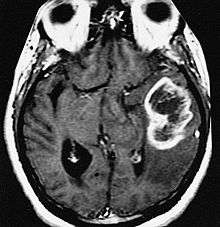

MRI showing a ring-enhancing lesion in the brain of a patient with glioblastoma multiforme

A ring-enhancing lesion is an abnormal radiologic sign on MRI or CT scans obtained using radiocontrast. On the image, there is an area of decreased density (see radiodensity) surrounded by a bright rim from concentration of the enhancing contrast dye. This can be a finding in numerous disease states. In the brain, it can occur with an early brain abscess as well as in Nocardia infections associated with lung cavitary lesions. In patients with HIV, the major differential is between CNS lymphoma and CNS toxoplasmosis, with CT imaging being the appropriate next step to differentiate between the two conditions.[1]